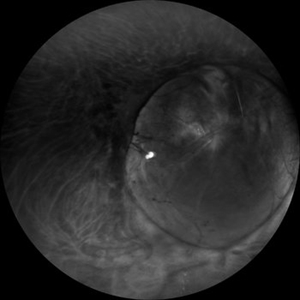

Widefield Retro Mode Image of Fundus Coloboma

Aug 31 2019 by Gayathri Mohan

Wide field image of a fundus coloboma taken in retro mode.

Photographer: Dr.Gayathri Mohan, Retina Foundation

Imaging device: Mirante, Nidek

Condition/keywords: coloboma, retromode